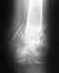

Без рентгенограмм невозможно уяснить, какой перелом шейки бедра был, какое положение отломков и фиксаторов было в результате операции, что изменилось со временем.